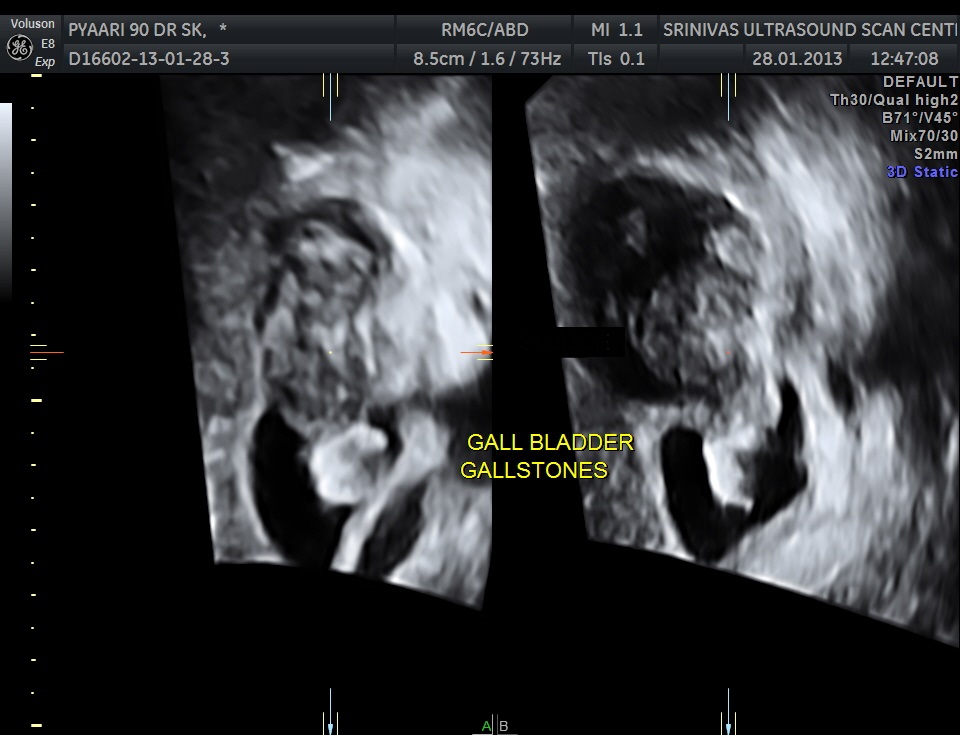

Ultrasound showed the following – Gallstone with irregular growth in the fundus of the gall bladder , above the phrygian cap.

The fundus shows irregular growth and a gallstone.